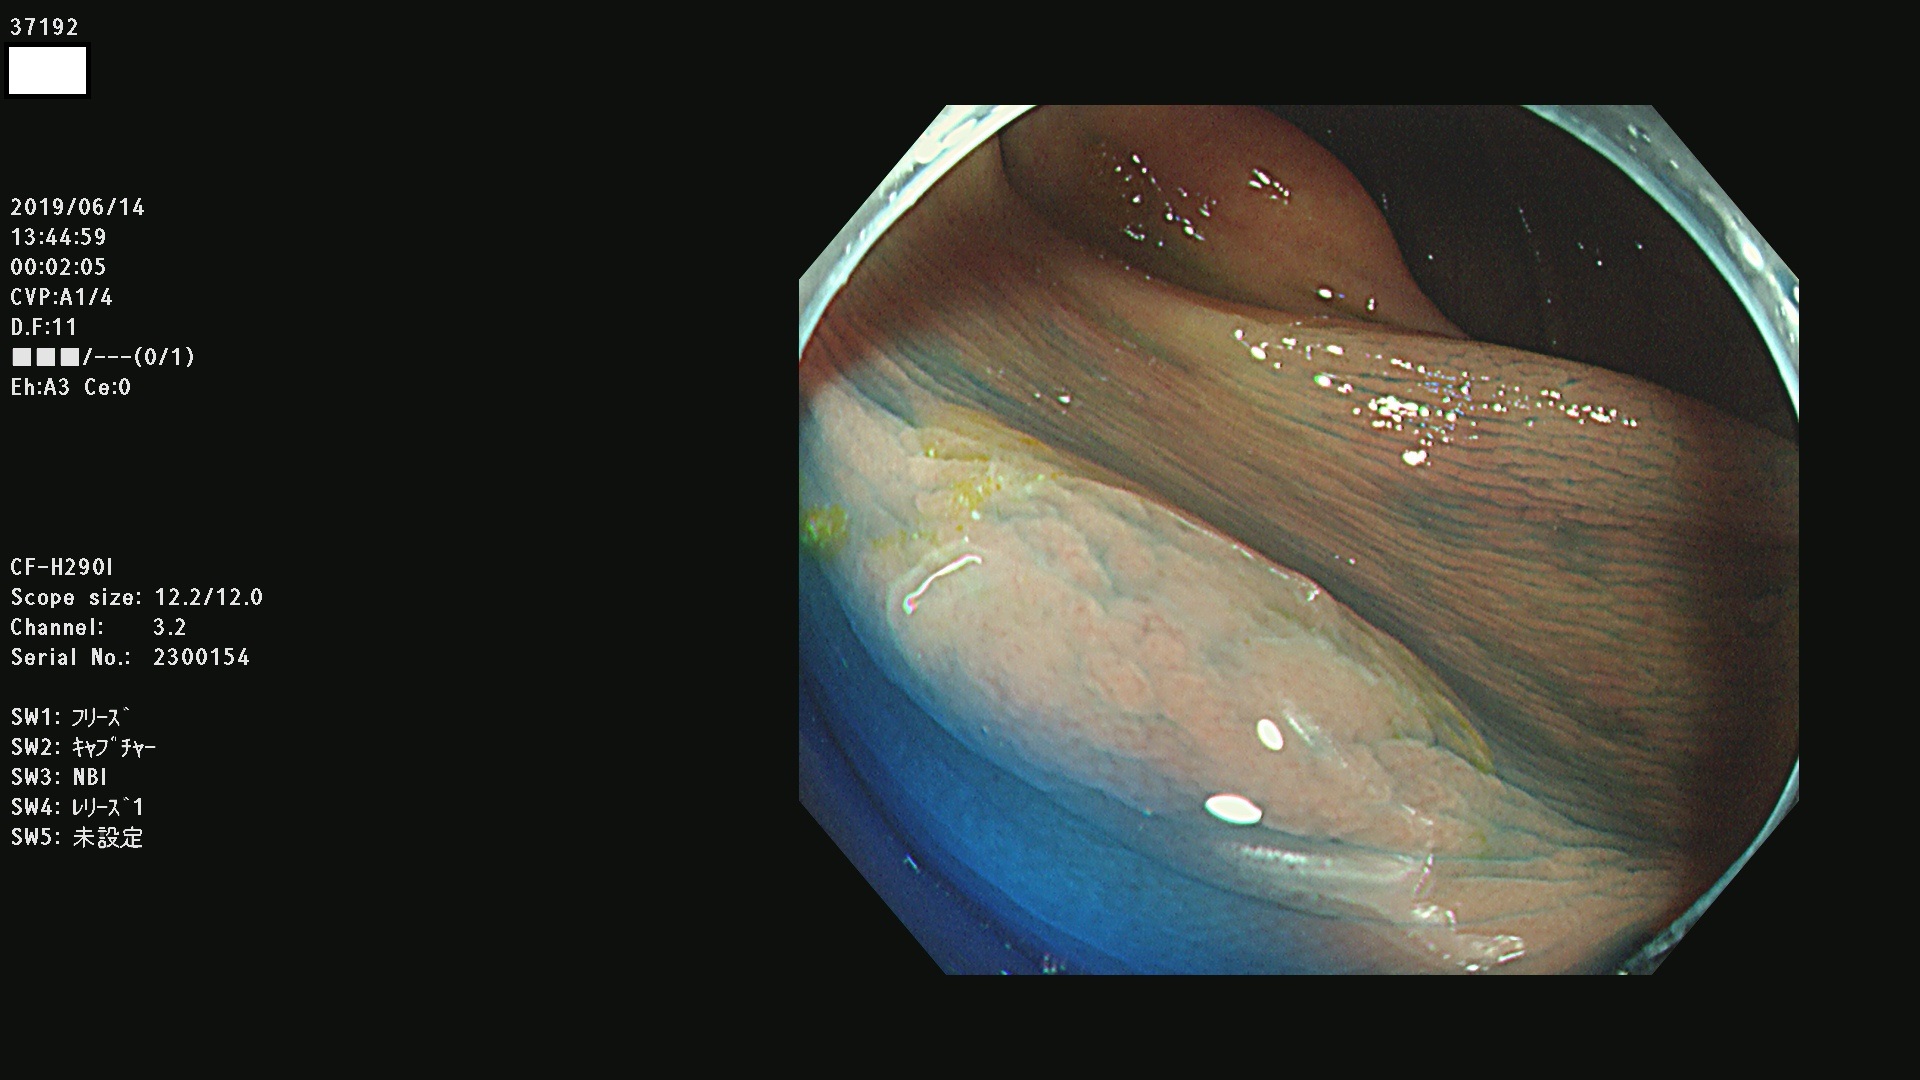

37100 37101 37102 37104 37106 37108 37110 37111 37112 37113 37115 37118(SSAPのみ) 37120 37122 37123 37124 37127(SSAPのみ) 37128(SSAPのみ) 37131 37132 37133 37134 37135 37139 37141 37142 37143 37144(SSAPのみ) 37145 37147(SSAPのみ) 37148 37149 37150 37153 37154 37157 37159 37161 37162 37163 37164 37165 37166 37167 37168 37169 37170 37171 37172 37173 37175(SSAPのみ) 37176 37177 37178 37180(SSAPのみ) 37181 37184 37185 37186 37187 37188 37189 37190 37192 37194 37197 37198

発見困難で危険性の高い平坦型病変(上記100名より抽出)